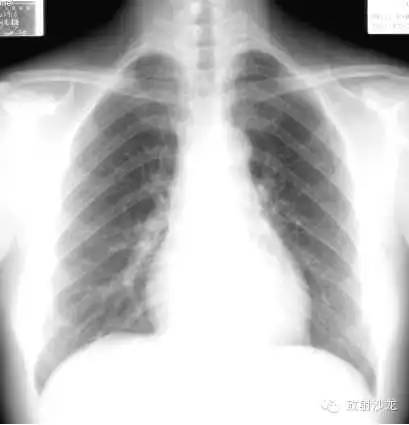

心脏远达片:多种体位投照,通过各房室、大血管边缘的位置、形态、大小,间接推测各房室的病生理改变。

心脏、大血管位于纵隔内,2/3位于胸腔中线左侧,1/3位于右侧。心尖在左下,心底在右后上,形成斜的纵轴。心脏两侧边缘与肺比邻,各房室间前后重叠,缺乏密度对比,故普通X线平片只能显示其轮廓而不能显示内部结构。

心脏大血管后前位投影 PA View

右心缘:上腔静脉或升主动脉,右房(膈低位右室)。

左心缘:主动脉弓;肺动脉段(心腰)。

左心室:相反搏动点位于肺动脉段与左室间左心耳1 cm。

侧位(Left lateral view),心影从后上向前下倾斜。心前缘: 1.升主动脉;2.右室漏斗部与肺动脉主干;3.右室心后缘;4.左心房;5.左心室。